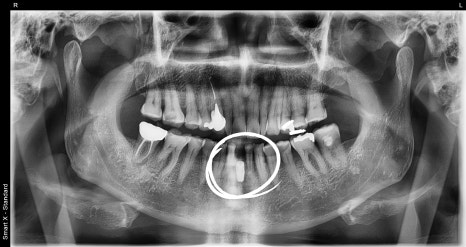

X-ray immediately after surgery

The loose tooth was extracted,

and implant placement and bone grafting were performed on the same day.

In the area where the jawbone was insufficient, bone grafting was used to support stable placement,

and a temporary tooth was also made to restore aesthetics.

The post-surgery X-ray showed that the implant had settled stably,

and the surrounding bone condition was being maintained well.